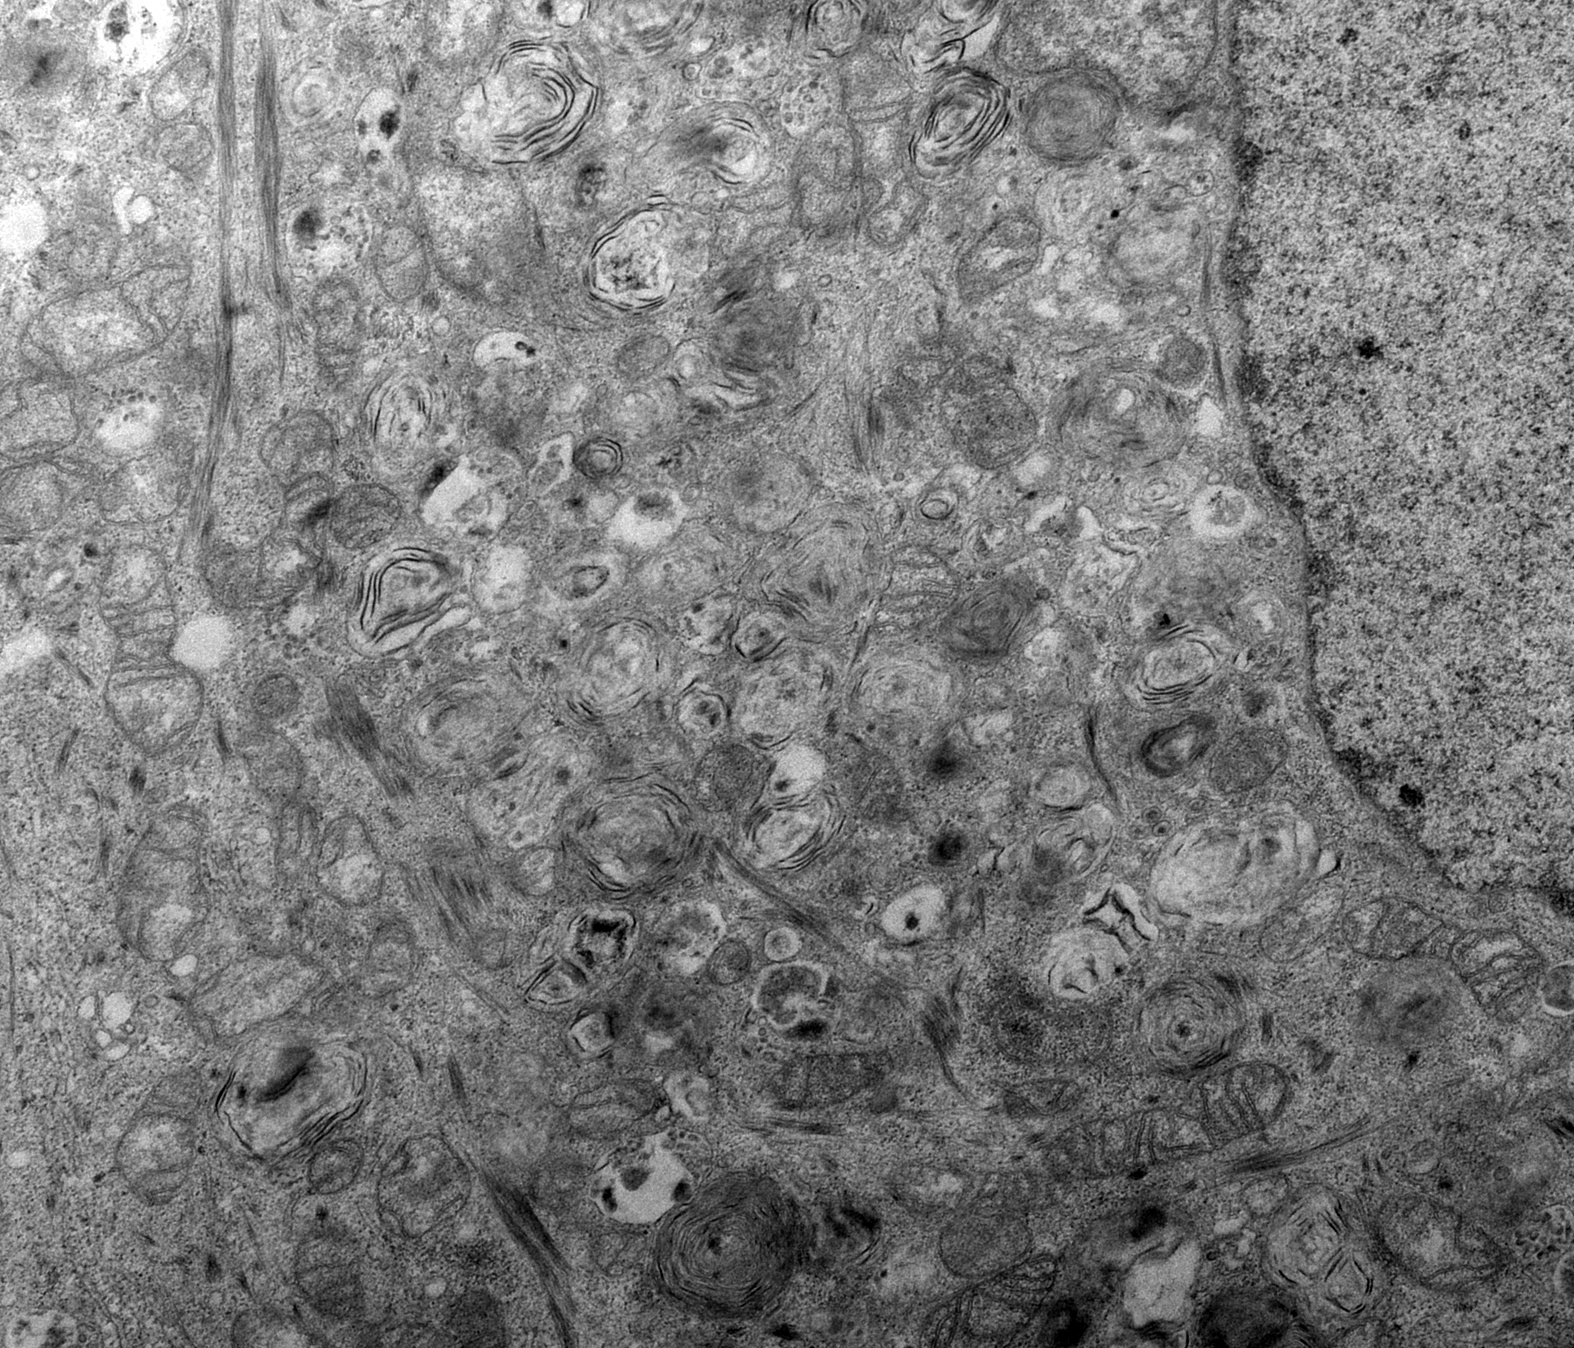

Should a radiologist be lecturing the president on Interferon response? This is what covid does to a cell.